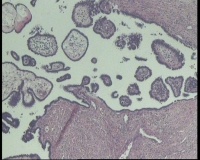

求会诊!左侧卵巢囊肿,够交界性浆液性囊腺瘤吗?

左侧卵巢囊肿大小约6.5x6.0厘米

碎囊壁组织5.0厘米一堆,壁厚0.1—0.4厘米,局灶囊壁见散在赘生物0.3,0.5厘米。另见完整小囊肿1.5x1.0厘米,无内容物,壁厚0.1厘米,内壁附0.8x0.7x0.4厘米赘生物,颗粒状

交界性浆液性乳头状囊腺瘤